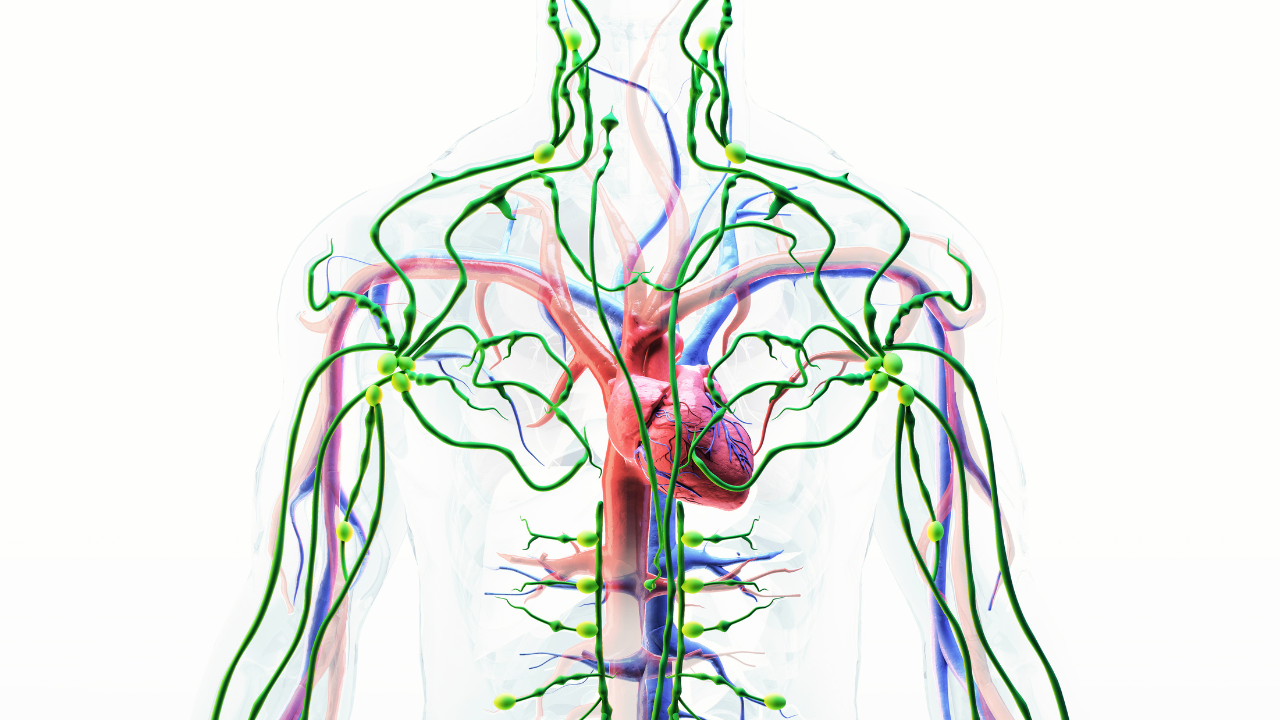

Our lymphatic system is similar to our body’s drainage and immune system. It assists in the movement of waste, toxins, and immune cells in the body. But when a person is under chronic stress, this system begins to disintegrate, getting tight, slow, and less efficient.

Let’s consider four actual ways that stress impacts your lymph vessels based on research.